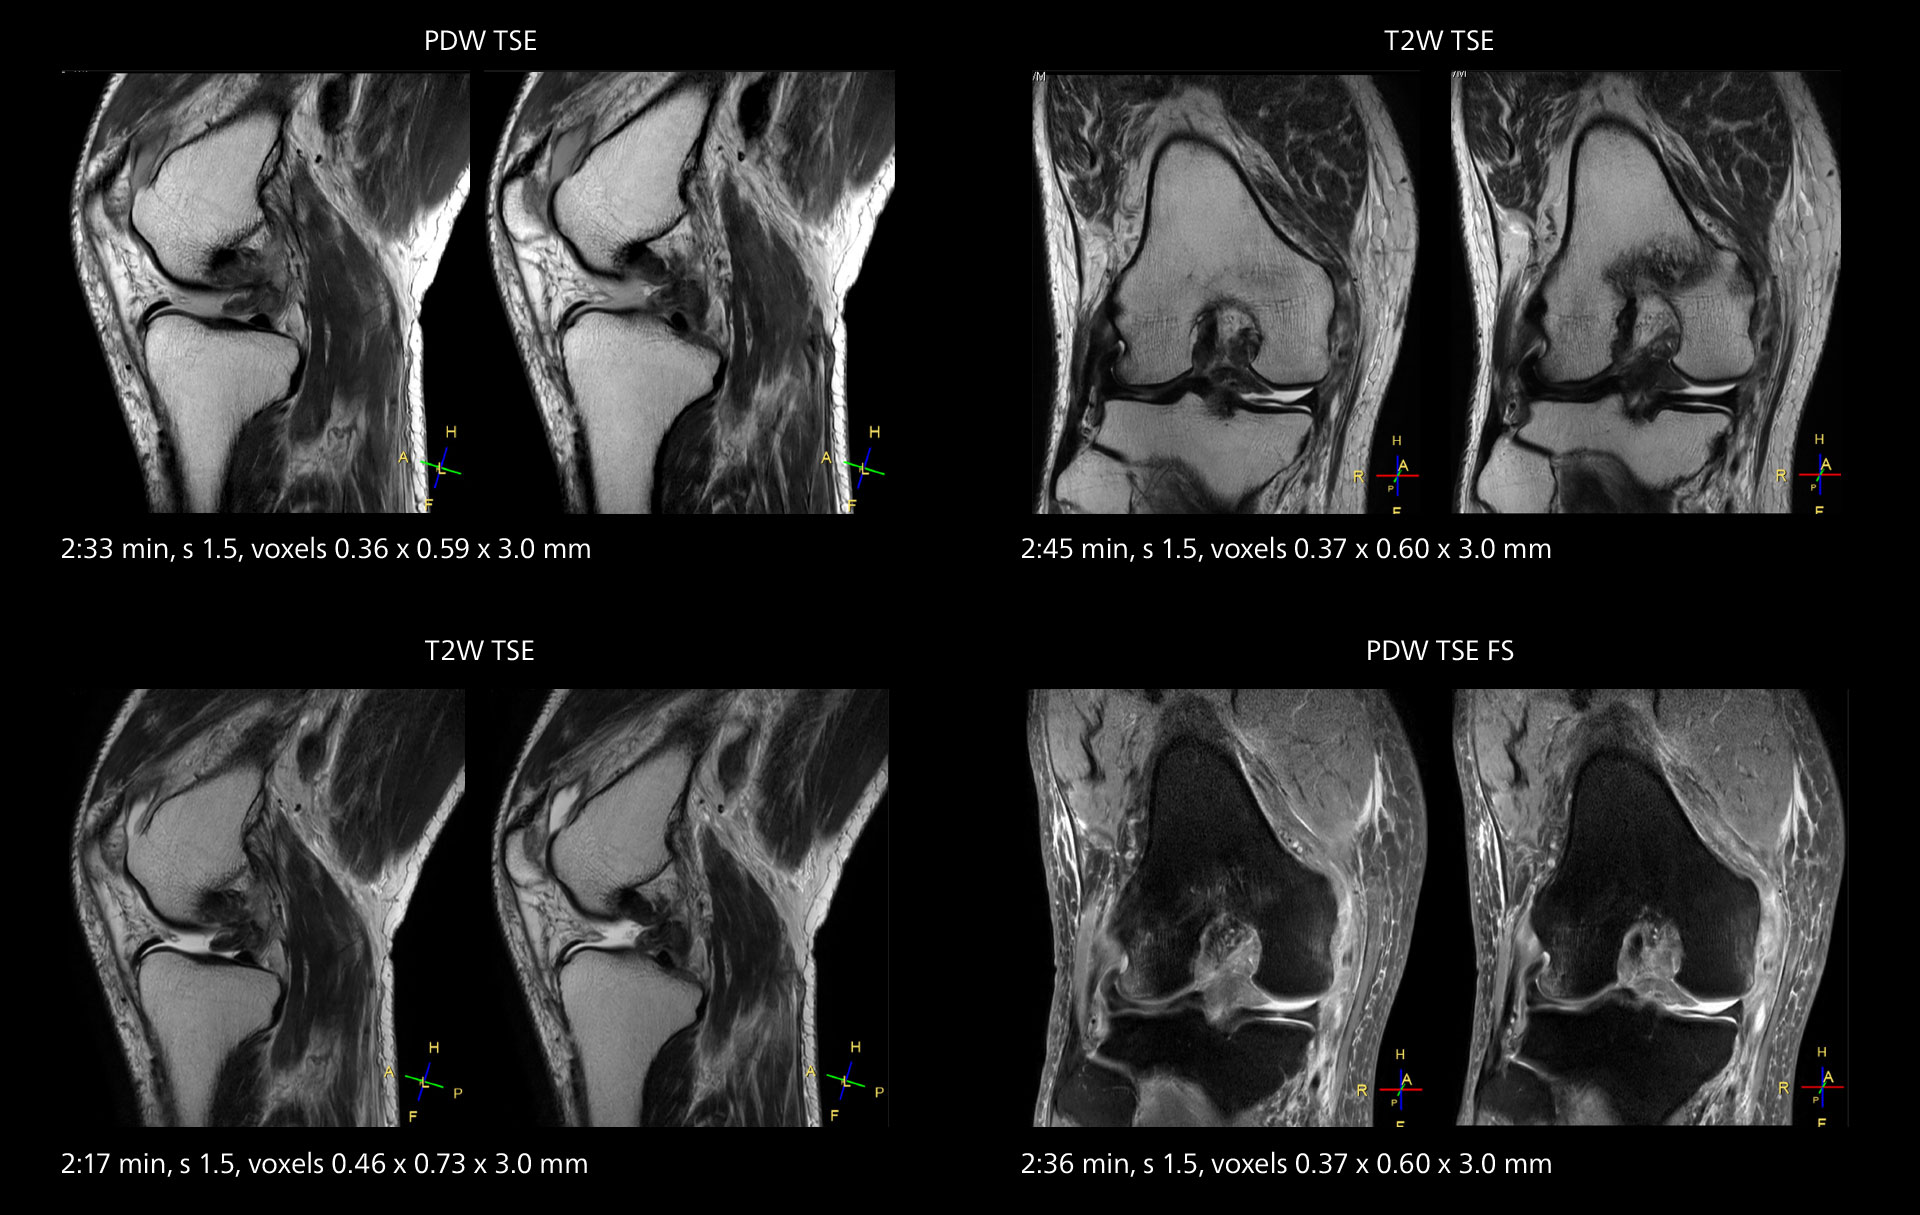

An example of increased imaging speed is in knee studies. “There is a definite scan time reduction for T2* mFFE and proton density TSE – both of these sequences benefit from much shorter repetition times,” he reports.

Overall, imaging time per sequence has been reduced since the Elition X upgrade. This can help reduce the risk of patient movement and the need for rescans.

Images showing a posterior cruciate ligament (PCL) tear, a detached medial collateral ligament (MCL) on the tibial side and an intact anterior cruciate ligament (ACL). SmartPath to Elition X helped reduce scan time compared to previous imaging while maintaining resolution.